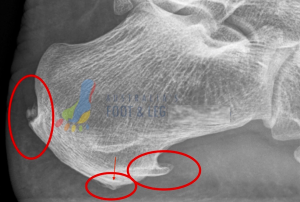

The Calf Muscle Attachment (Posterior Heel Spur):

- The number one muscle that is tight in at least 95% (anecdotal figure) of patients is the calf muscle. As a result on imaging we can typically see spurring, or at least excess bone deposit at the rear of the heel where your achilles tendon attaches to the heel bone. You can find an example of this shown on the foot x-ray below highlighted by the red circle.

The Arch Muscle Attachment (Plantar Heel Spur):

- the next common muscles that are tight in many patients experiencing heel pain are the arch muscles. Please be aware there are multiple arch muscles in the foot – here we’re over-simplifying the topic for ease of illustration but many share a similar attachment point at the bottom of the heel bone. You can find an example of this shown on the foot x-ray below highlighted by the red circle.

The Arch Ligament Attachment (Plantar Fascial Heel Spur):

- the final point that is rarely seen by itself but still worth a mention as it is a sign of long-standing plantar fascia attachment irritation of the heel bone is what we call the plantar fascial heel spur. This attachment point is the true attachment of the plantar fascia and irritation here is a sign of excessive strain through the plantar fascia. Bear in mind your plantar fascia is a strong ligament (bone to bone not muscle to bone with a tendon) so when this is pulling excessively your foot muscles have ‘given up’. You can find an example of this shown on the foot x-ray below highlighted by the arrow pointing at the red circle.